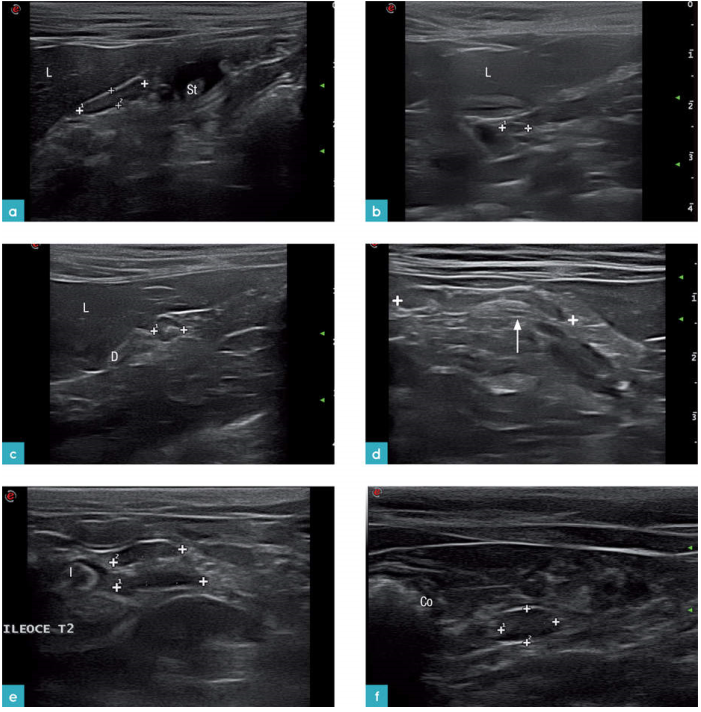

图5显示了猫腹部淋巴结的分布情况。淋巴结是根据脏层和壁层来划分的。四个壁层淋巴中心包括腰荐淋巴中心,髂骶淋巴中心,腹股沟淋巴中心,坐骨淋巴中心。三个脏层淋巴中心包括下腹淋巴中心,前肠系膜淋巴中心,后肠系膜淋巴中心。易见的脏层淋巴结有胃淋巴结,肝脏淋巴结,胰十二指肠淋巴结,空肠淋巴结,回盲淋巴结,结肠淋巴结(图6)。壁层淋巴结里易见的淋巴结包括有髂中淋巴结和腹股沟浅淋巴结(图7)脏层淋巴结中不易见的淋巴结包括有脾脏淋巴结和后肠系膜淋巴结(图8)。壁层淋巴结中不易见的淋巴结包括有腰动脉淋巴结,肾淋巴结,髂内淋巴结,骶骨淋巴结,尾部淋巴结,尾上腹淋巴结。浅表淋巴结例如腹股沟浅淋巴结和髂中淋巴结呈现细长的纺锤状。淋巴结的边缘规则,被膜产回声,它的实质相对于脂肪来讲是无回声的或是低回声的。腹部较深的淋巴结中只有空肠淋巴结,后肠系膜淋巴结是狭长的形状,其他的则为卵圆形。淋巴结的实质部分比脂肪组织的回声低,外周被脂肪组织包裹,清晰的边界。表1为腹部淋巴结的位置与大小。

腹部器官的血供是从主动脉的分支而来(下腹动脉,前肠系膜动脉,肾动脉,旋髂深动脉,髂外动脉,髂内动脉,骶中动脉)。腹腔的静脉血液有两个走向,一个走向是汇入后腔静脉,另一个走向是汇入门静脉。测量主动脉和CVC的血流速度时,需要使探头的切面与腰椎的长轴平行。腹主动脉从膈下行到第六腰椎的水平面,位置稍稍偏中线的左侧,是有高回声的管壁,内部是无回声的液体(图9a和9b),横截面上会更加清晰。二维扫查可以见到主动脉所有的分支。后腔静脉位于腹主动脉的右侧在超声形态上与腹主动脉相似。后腔静脉较腹主动脉而言,更容易被探头压扁(图9c)。门静脉位于肝门,它的分支有胃十二指肠静脉,脾静脉,前肠系膜静脉和后肠系膜静脉。门静脉位于腹中线偏右(图9d)。